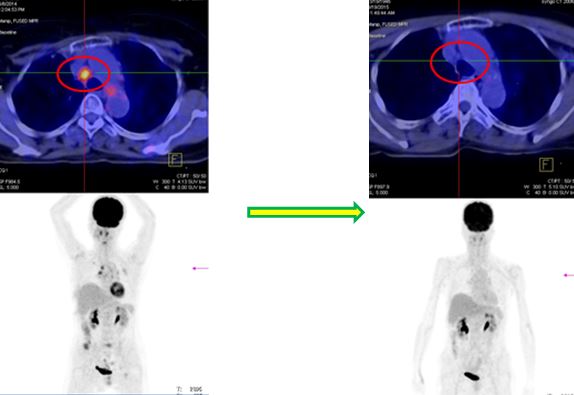

Hình ảnh PET/CT trước và sau 6 chu kỳ điều trị với Cisplatin-Pemetrexed

Trước điều trị: Hạch cạnh phải khí quản KT 1,2x2,0 cm, Max SUV=5,08 | Sau điều trị: Hạch cạnh phải khí quản tan hết |